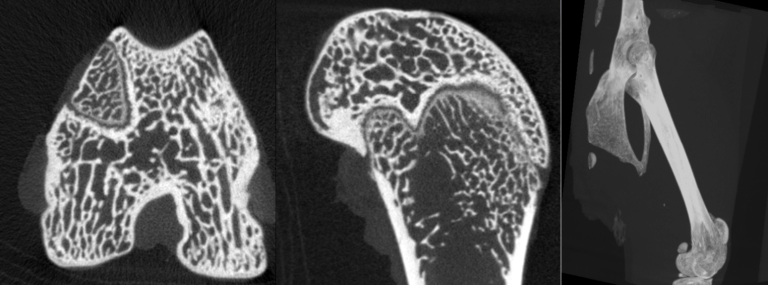

Milabs CT is capable of fast scanning and ultra-high-resolution scanning under low-dose X-rays, and the highest resolution can reach 10um.

- bone image